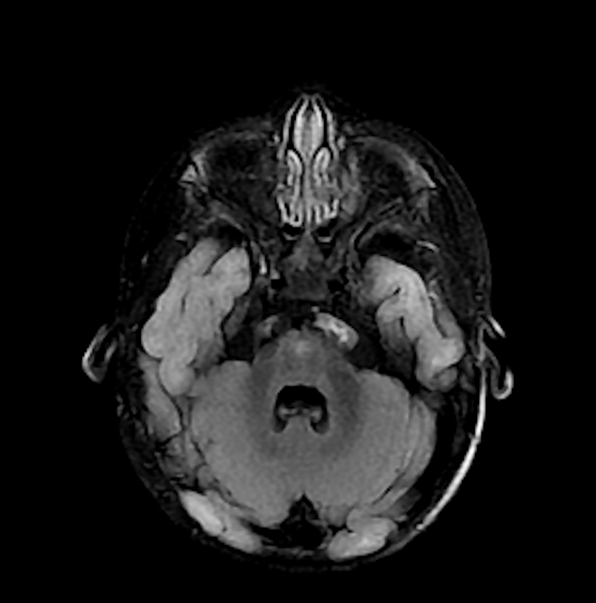

Unilateral Moyamoya Disease in an Adolescent Female of Non-Asian Descent: A Case Report

Aaron Peterson, BS, Trinity Puno, BS, Joshua Levy, MD, Angus Cheng, DO, Jabre Millon, MD, Tim Stone, MD, Isaac Wang, DO, Rajpaul Gill, MD, Millie Pal, DO, Kyle Mefferd, PhD, Denise Vidal , MPH, Angelina Rodriguez, MD, Upinder Singh, MD

1-7